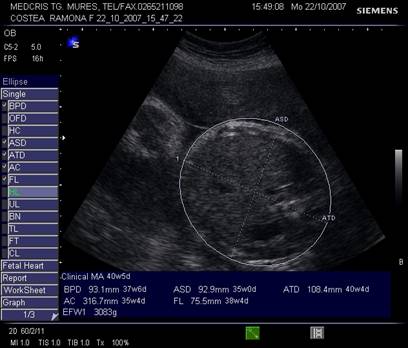

Abdomenul - Hansmann a definit planul de referinta transversal pe trunchiul fetal, cu ficatul, stomacul si vena ombilicala la trecerea in sinusul portal, mult in spatele peretelui abdominal.[4]

Cei

trei parametrii ATD, ASD si AC se vor masura in acest plan, de la exterior la

exterior. Circumferinta abdominala va fi masurata individual sau calculata

automat dupa masurarea celor doua diametre abdominale.

Fig. nr. 200 Masurarea diametrelor transversale abdominale (ATD; ASD) si a circumferintei abdominale ( AC )